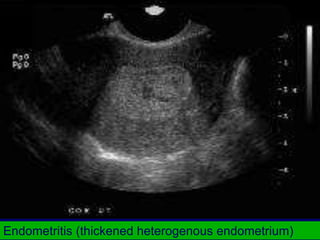

Endometritis (thickened heterogenous endometrium)